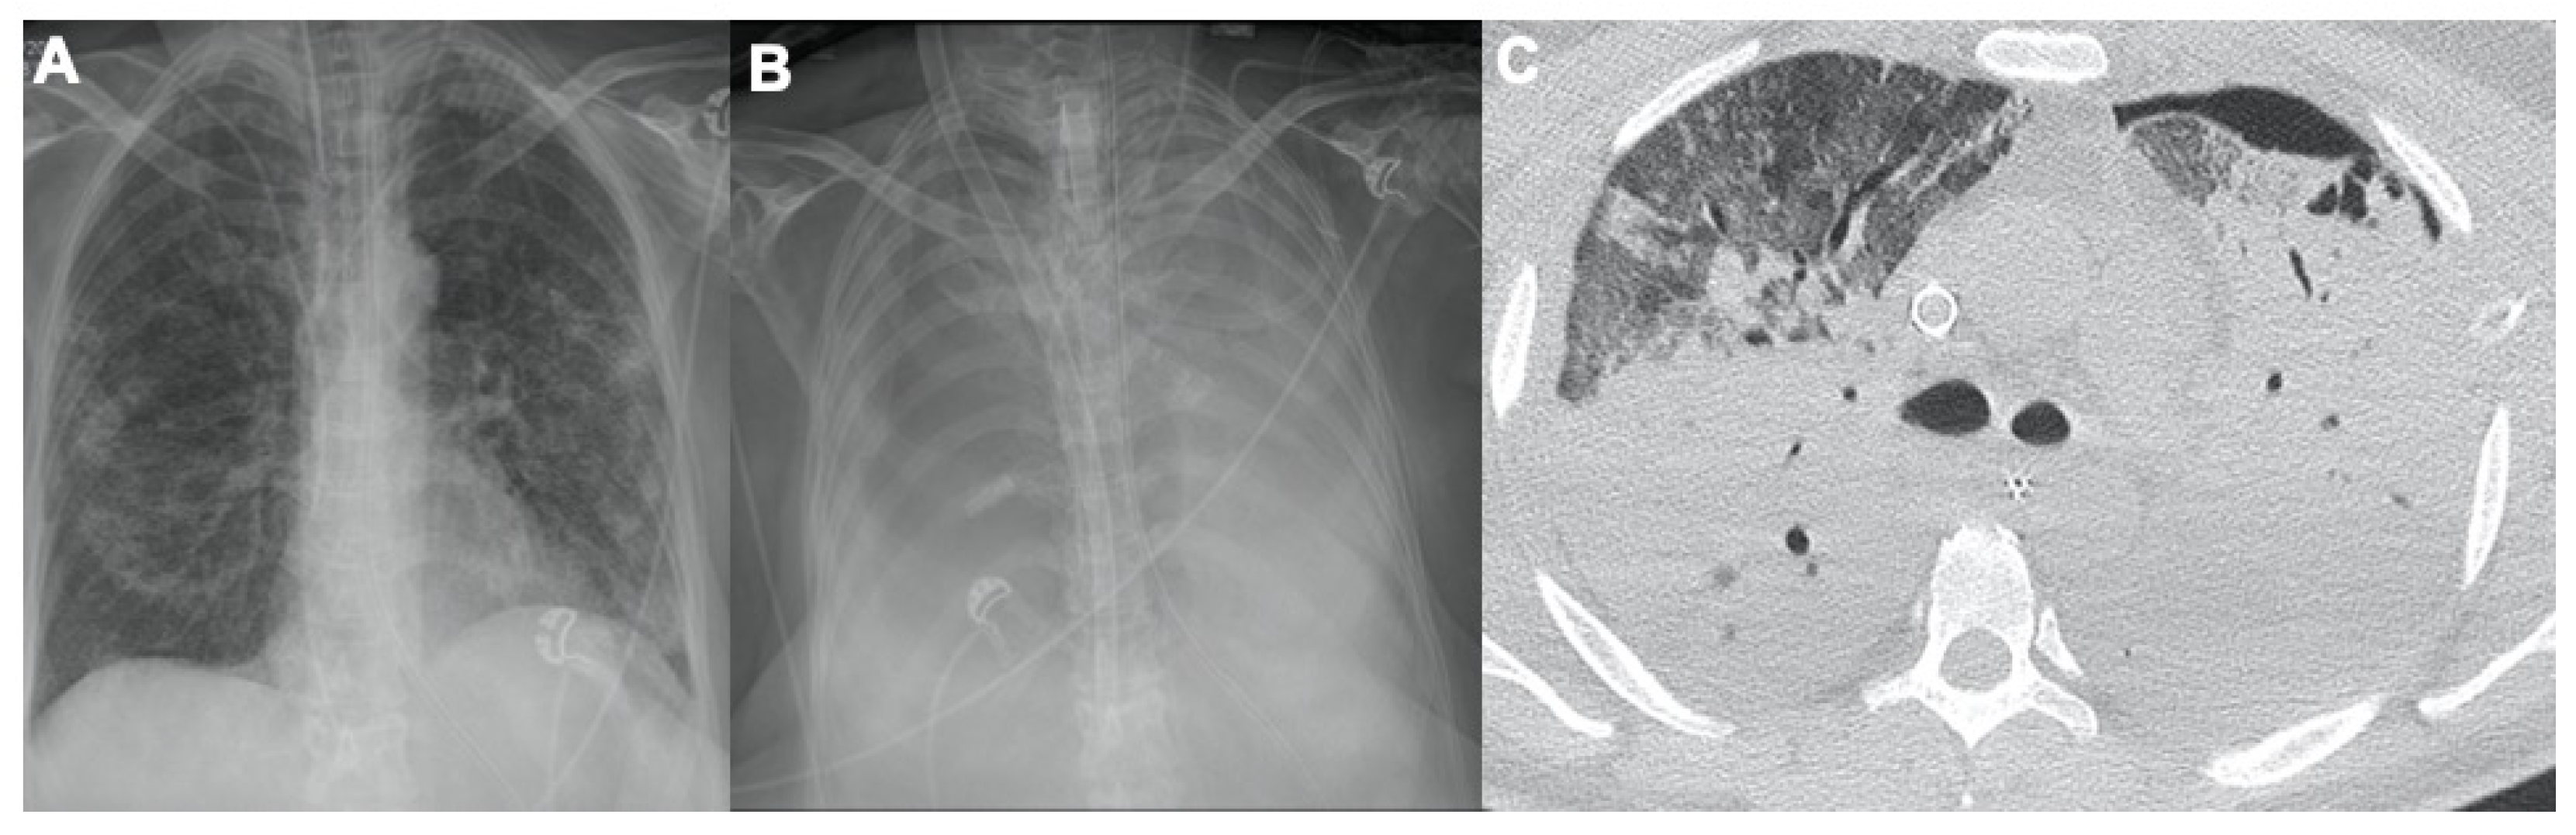

2. COVID-19 and Lung Disease

2.1. Pneumonia